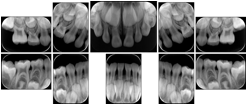

- OO-1. Intra-oral Full Mouth Series Structured Display